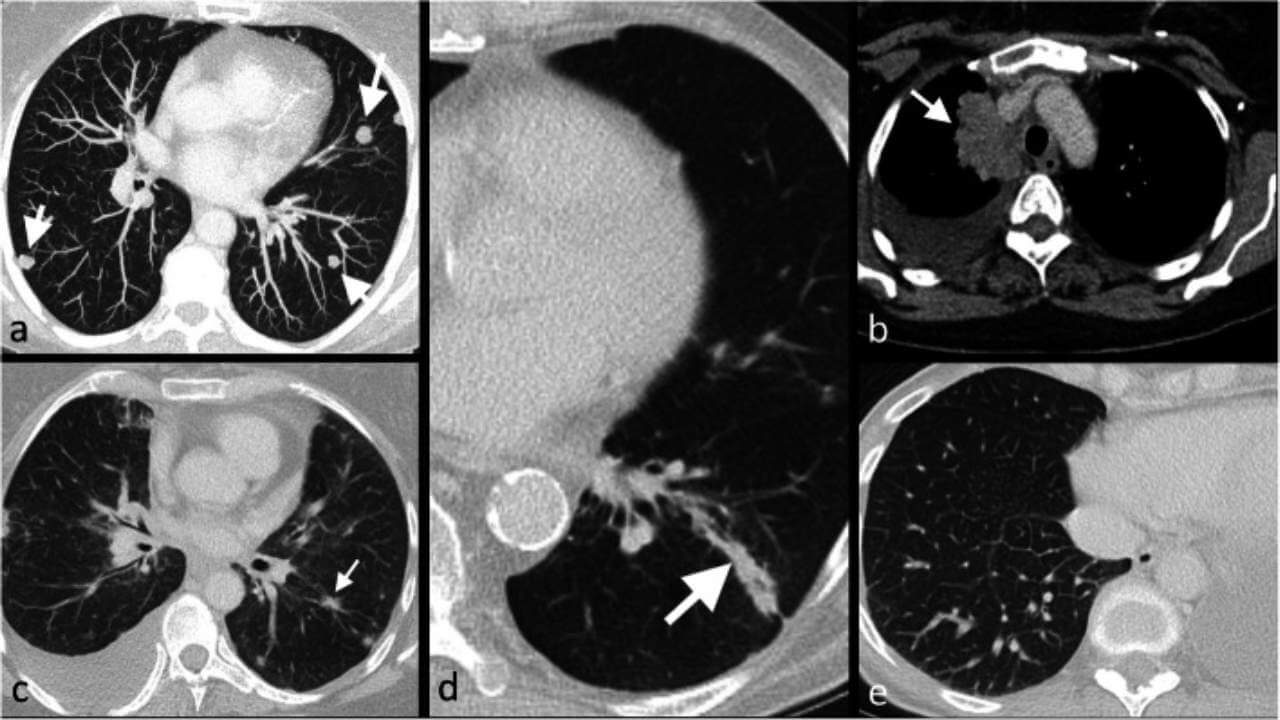

When lung metastases are suspected, a chest CT scan or PET scan is often ordered. If the scan reveals a tumor and the doctor has confirmed that it is cancerous, it is also important to confirm whether it is primary lung cancer – cancer that begins in the lungs – or breast cancer that has spread to the lungs. The treatment of primary lung cancer is different from treat metastatic breast cancer diagnosis that has spread to the lungs.

Diagnostic tools include Chest CT, PET-CT, MRI (in selected cases), biopsy (if necessary to clarify the diagnosis), molecular genetic, cancer markers and immunohistochemical tests.